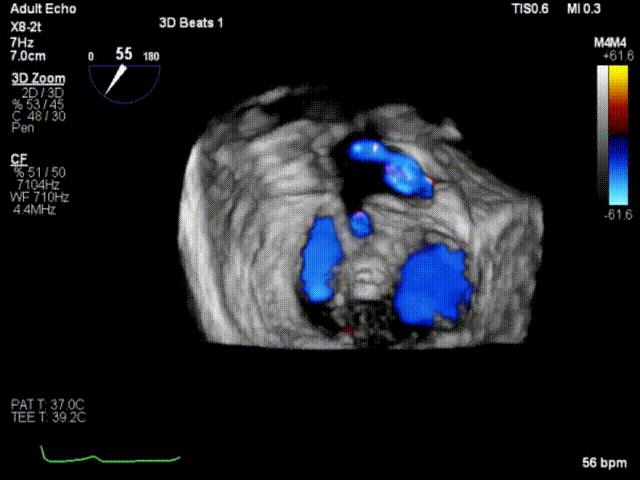

术后即刻超声心动图

术后即刻超声3D

手术运用DSA与三维经食道超声心动图监测,通过患者股静脉穿刺房间隔途径建立夹合器输送轨道,将夹合器送进左心房,借助夹合器输送系统通过病变的二尖瓣部位,在心脏不停跳的状态下快速完成二尖瓣脱垂瓣叶的破获和夹合,夹合位置满意,超声提示反流降至1+,遂释放夹合器,反流最终程度为1+,结束手术,手术过程耗时一小时左右。